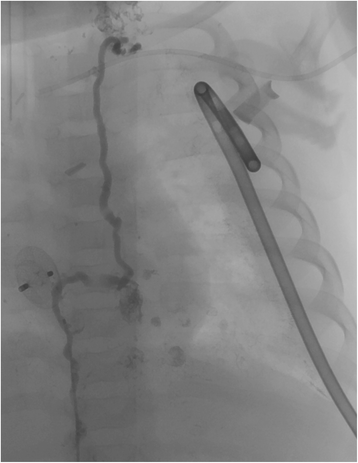

Pre TD embolization in patient #3. Pre TD embolization imaging confirms MR lymphangiography with lymphatic drainage into left pleural space